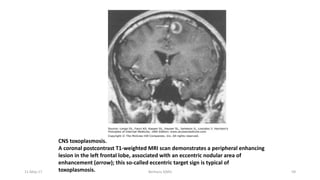

CNS Toxoplasmosis – Dx & dDx

Diagnosis - MRI - multiple lesions - in some cases only a

single lesion is seen.

 Pathologically - inflammation and central necrosis and, as a

result, demonstrate ring enhancement on contrast MRI or on

double-dose contrast CT.

 There is usually evidence of surrounding edema.

dDx of single or multiple enhancing mass lesions in the HIV-

infected patient includes primary CNS lymphoma and, less

commonly, TB or fungal or bacterial abscesses.

Definitive Dx - brain biopsy.

CNS toxoplasmosis.

A coronal postcontrast T1-weighted MRI scan demonstrates a peripheral enhancing

lesion in the left frontal lobe, associated with an eccentric nodular area of

enhancement (arrow); this so-called eccentric target sign is typical of

toxoplasmosis.